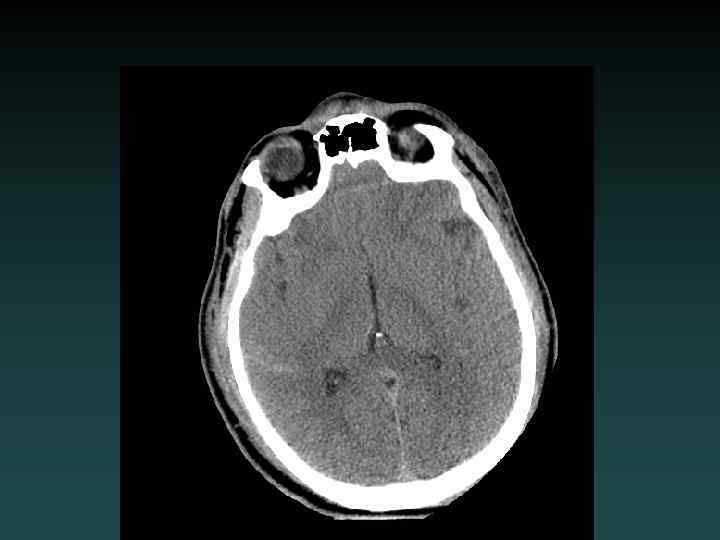

Anoxic brain injury • Loss of Gray-White • Progresses with worsening edema • Pseudo. SAH • Hydrocephalus • Cisterns compressed